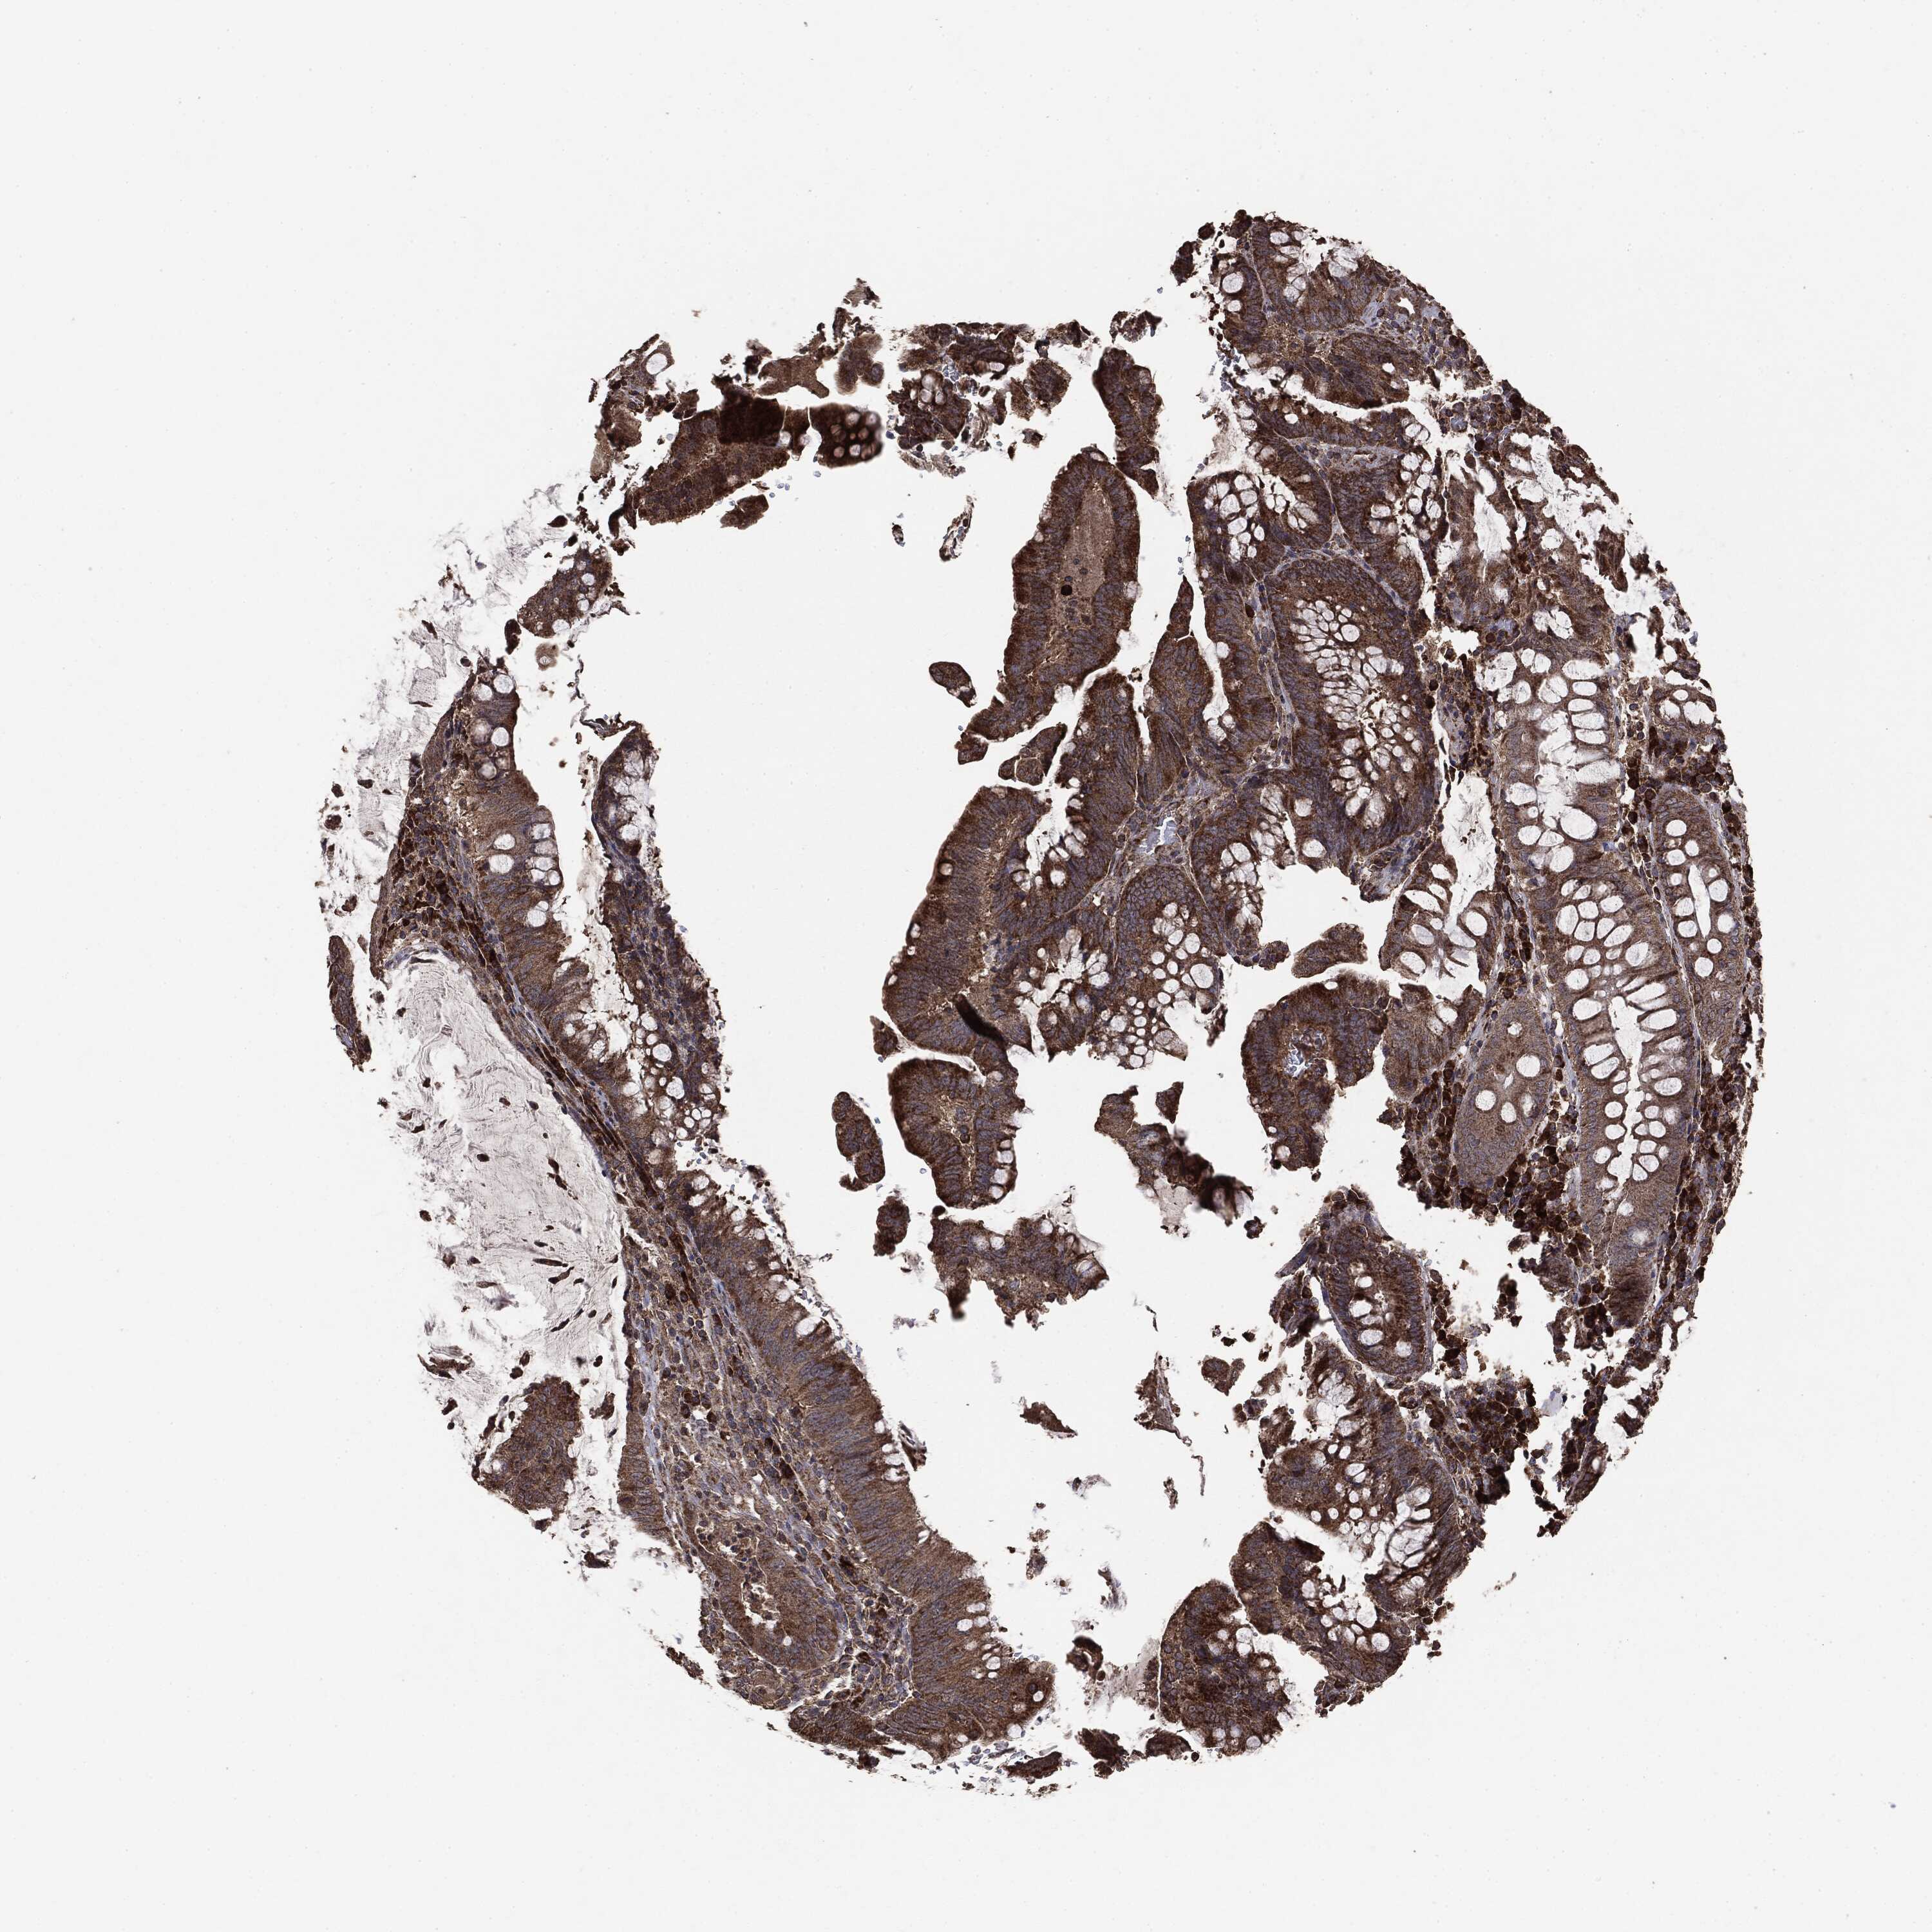

CANCER COLORECTAL CANCER Show tissue menu

Colorectal cancer

Human cancer

Colon adenocarcinoma